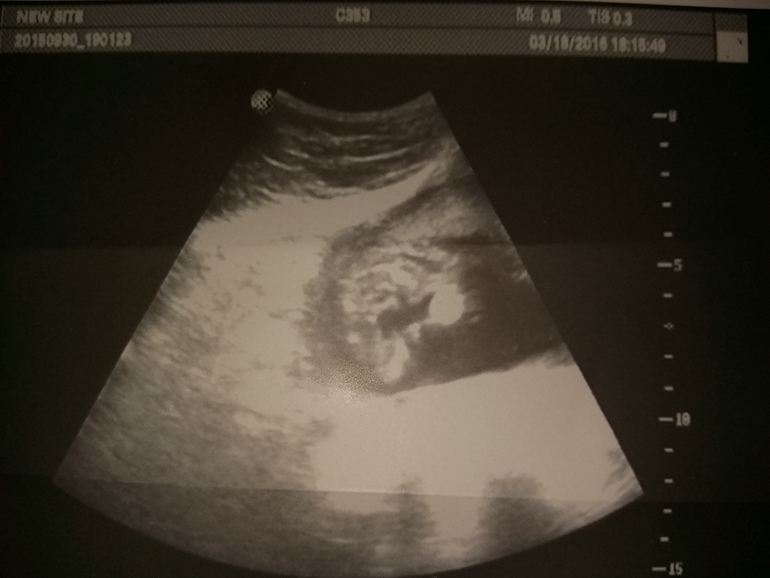

18 недель узи

Добрый вечер, девочки. Вот пришла сегодня с узи.) Сказали- девочка. С

ама особо разобрать на могу. Как вы думаете?